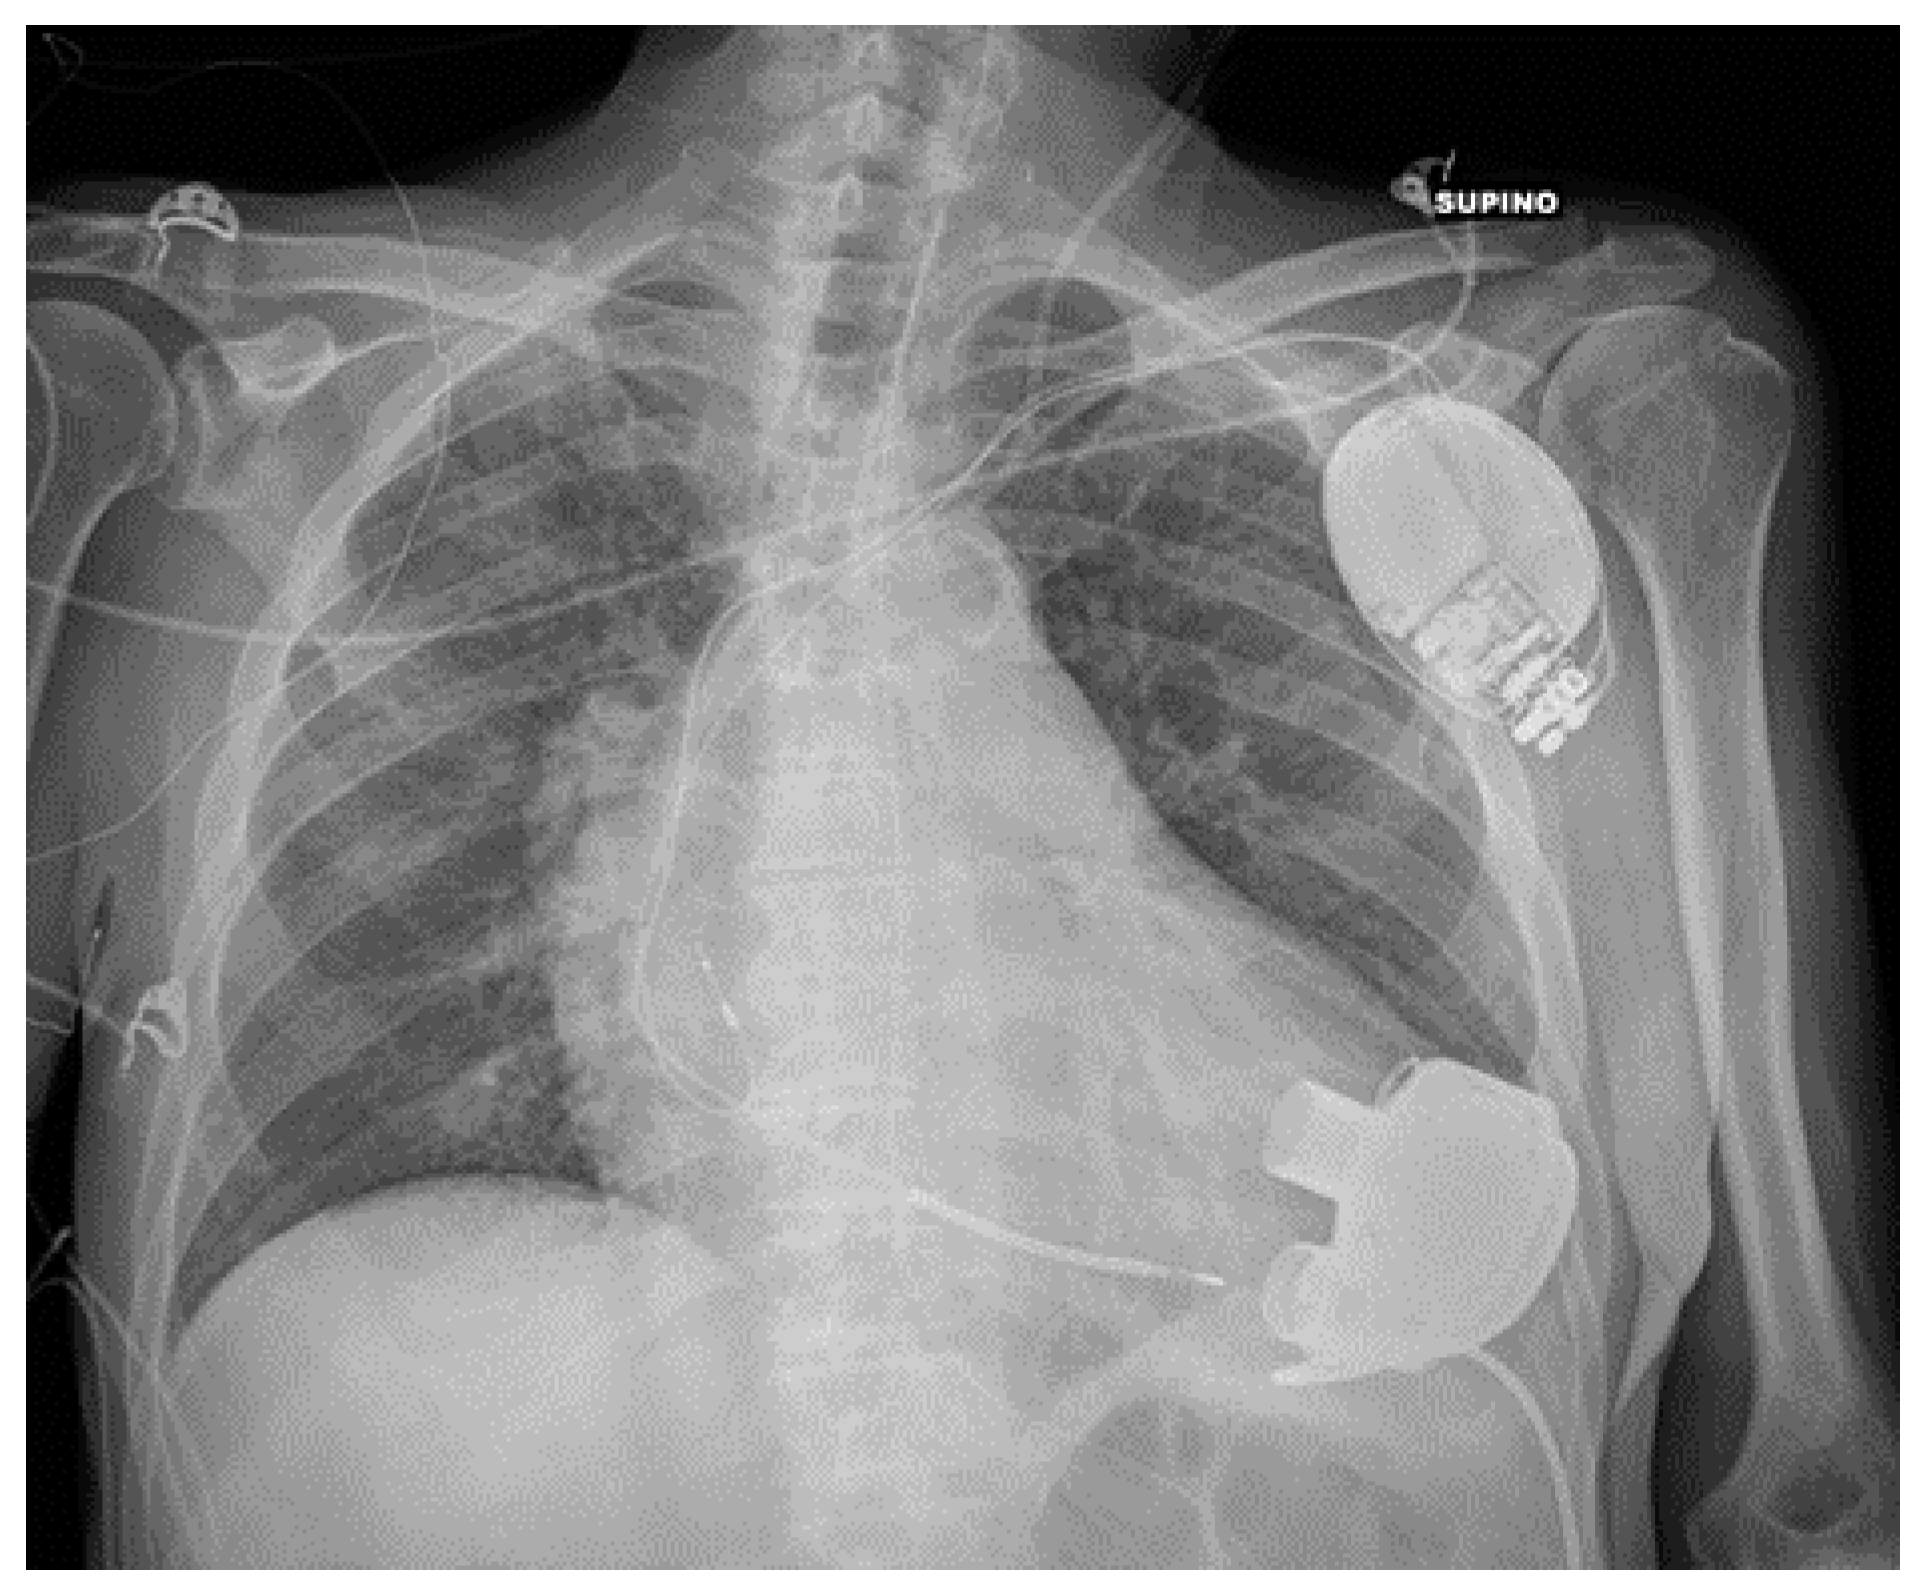

5.3. Ventricular Assistance Devices (VADs)

VADs are mechanical circulatory support devices that can be implanted both in the right (RVAD) or left (LVAD) ventricle; in some cases, RVAD and LVAD can be placed together.

These devices are surgically implanted, with a pump communicating with the ventricle through an inflow cannula while an outflow cannula delivers blood to the aorta (in the case of LVAD) (Figure 15) or to the pulmonary artery (in the case of RVAD) [23].

Figure 15.

Properly positioned LVAD. The image also shows an AICD, a left jugular CVC and a nasogastric tube.

A CXR can provide information regarding the correct positioning of the cannula. Bleeding from the insertion point can cause hemopericardium, leading to cardiac tamponade or hemothorax; other possible complications of VADs (thrombosis/venous thromboembolism, cardiac arrhythmias, solid organ dysfunction, driveline infections) are not detectable on a CXR [24,25,26,27].

Frequently, the pump of the VAD covers part of the thorax on a CXR, therefore making it difficult for the radiologist to evaluate lung parenchyma and pleural space in that particular site (Table 4).